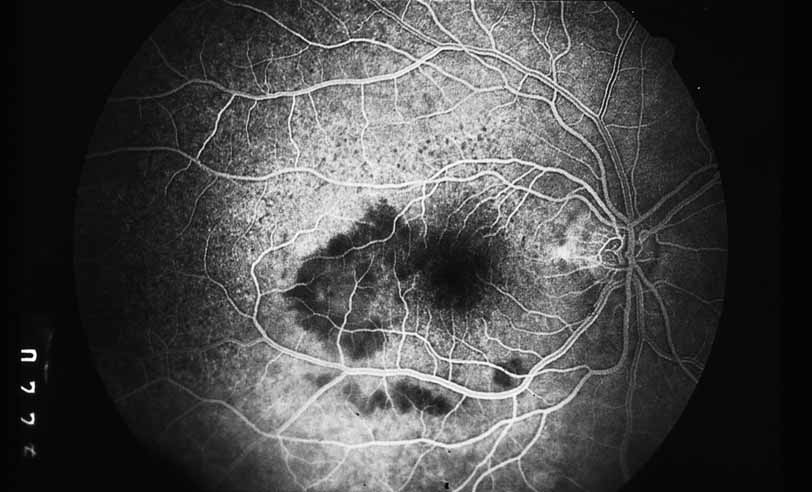

A third instance in which fluorescein angiography concentrating on the optic nerve may be helpful is in eyes with vascular engorgement of the optic nerve, especially with media opacities. Fluorescein angiography may help the clinician distinguish abnormally leaking capillaries from neovascularization. In acute multifocal hemorrhagic retinal vasculitis, optic nerve involvement is common in the early stages of the disease, 47 with optic nerve disc neovascularization seen later (see Figs. 10, 11, 12, and 13). Another fluorescein angiographic clue to the distinction between optic disc vessel engorgement and true neovascularization is the presence of associated large zones of retinal capillary nonperfusion such as those seen in sarcoidosis (see Figs. 14 and 15),34–40 acute multifocal hemorrhagic retinal vasculitis (see Figs. 10 and 11),47 or Eale disease (see Figs. 16 and 17).48–52

Fig. 10 Acute multifocal hemorrhagic retinal vasculitis. A middle-aged man presented with the picture of multiple branch vein obstructions and low-grade intraocular inflammation.

Fig. 11 Acute multifocal hemorrhagic retinal vasculitis. Fluorescein angiogram confirms the presence of associated retinal capillary non-perfusion without neovascularization at the onset of the disease.